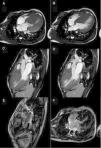

En la cardiorresonancia magnética, se encontró hipertrofia biventricular severa concéntrica simétrica (fig. 3a y b) con movimiento sistólico anterior de la válvula mitral (SAM) (fig. 3c y d). Mediante contraste con secuencias de viabilidad y realce tardío se visualizan extensas áreas de tejido conectivo infiltrante no viable (fig. 3e y f).

CRM en secuencias Balanced Fast Field Echo, cortes axial y coronal, en sístole y diástole. Hipertrofia biventricular severa concéntrica simétrica (a y b) con movimiento sistólico anterior de la válvula mitral (SAM) (c y d). Con secuencias de viabilidad y realce tardío se visualizan extensas áreas de tejido conectivo infiltrante no viable (e y f).